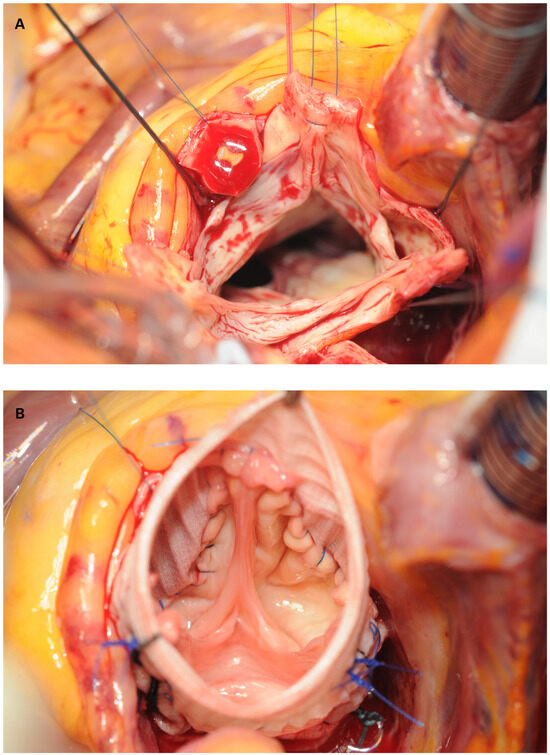

Myocardial infarction with nonobstructive coronary arteries (MINOCA): Myocardial infarction (MI) with non-obstructive coronary arteries (MINOCA) is defined as MI according to the fourth universal definition of MI [1] without coronary stenosis ≥50% on...